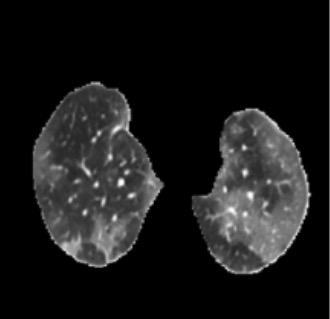

In the field of medical imaging, particularly in tasks related to early disease detection and prognosis, understanding the reasoning behind AI model predictions is imperative for assessing their reliability. Conventional explanation methods encounter challenges in identifying decisive features in medical image classifications, especially when discriminative features are subtle or not immediately evident. To address this limitation, we propose an agent model capable of generating counterfactual images that prompt different decisions when plugged into a black box model. By employing this agent model, we can uncover influential image patterns that impact the black model's final predictions. Through our methodology, we efficiently identify features that influence decisions of the deep black box. We validated our approach in the rigorous domain of medical prognosis tasks, showcasing its efficacy and potential to enhance the reliability of deep learning models in medical image classification compared to existing interpretation methods. The code will be publicly available at https://github.com/ayanglab/DiffExplainer.